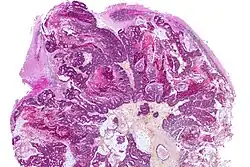

In addition to imaging, biopsy is often recommended to confirm diagnosis.[6] The diagnosis of brain metastases typically follows a diagnosis of a primary cancer.[10] Occasionally, brain metastases will be diagnosed concurrently with a primary tumor or before the primary tumor is found.